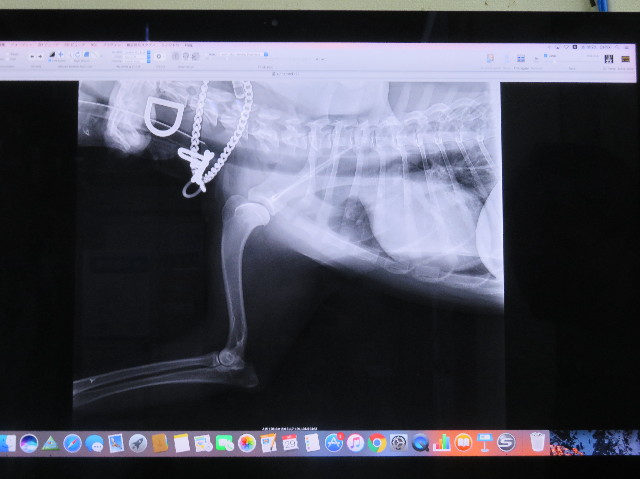

初めての血液検査の結果

上段の高い低いは特に問題ないそうですが

下段の総コレステロールが高いのはちょと問題(汗)

うちは、べべちゃんももいちゃんもみんな、だいたいずーっと総コレステロールが高かったから.....もにはまだ生後10ケ月だし活発ですごく良く動くのにすでに高いから、これはやっぱり食事のせいも大きいんだろうねr(^ω^*)))